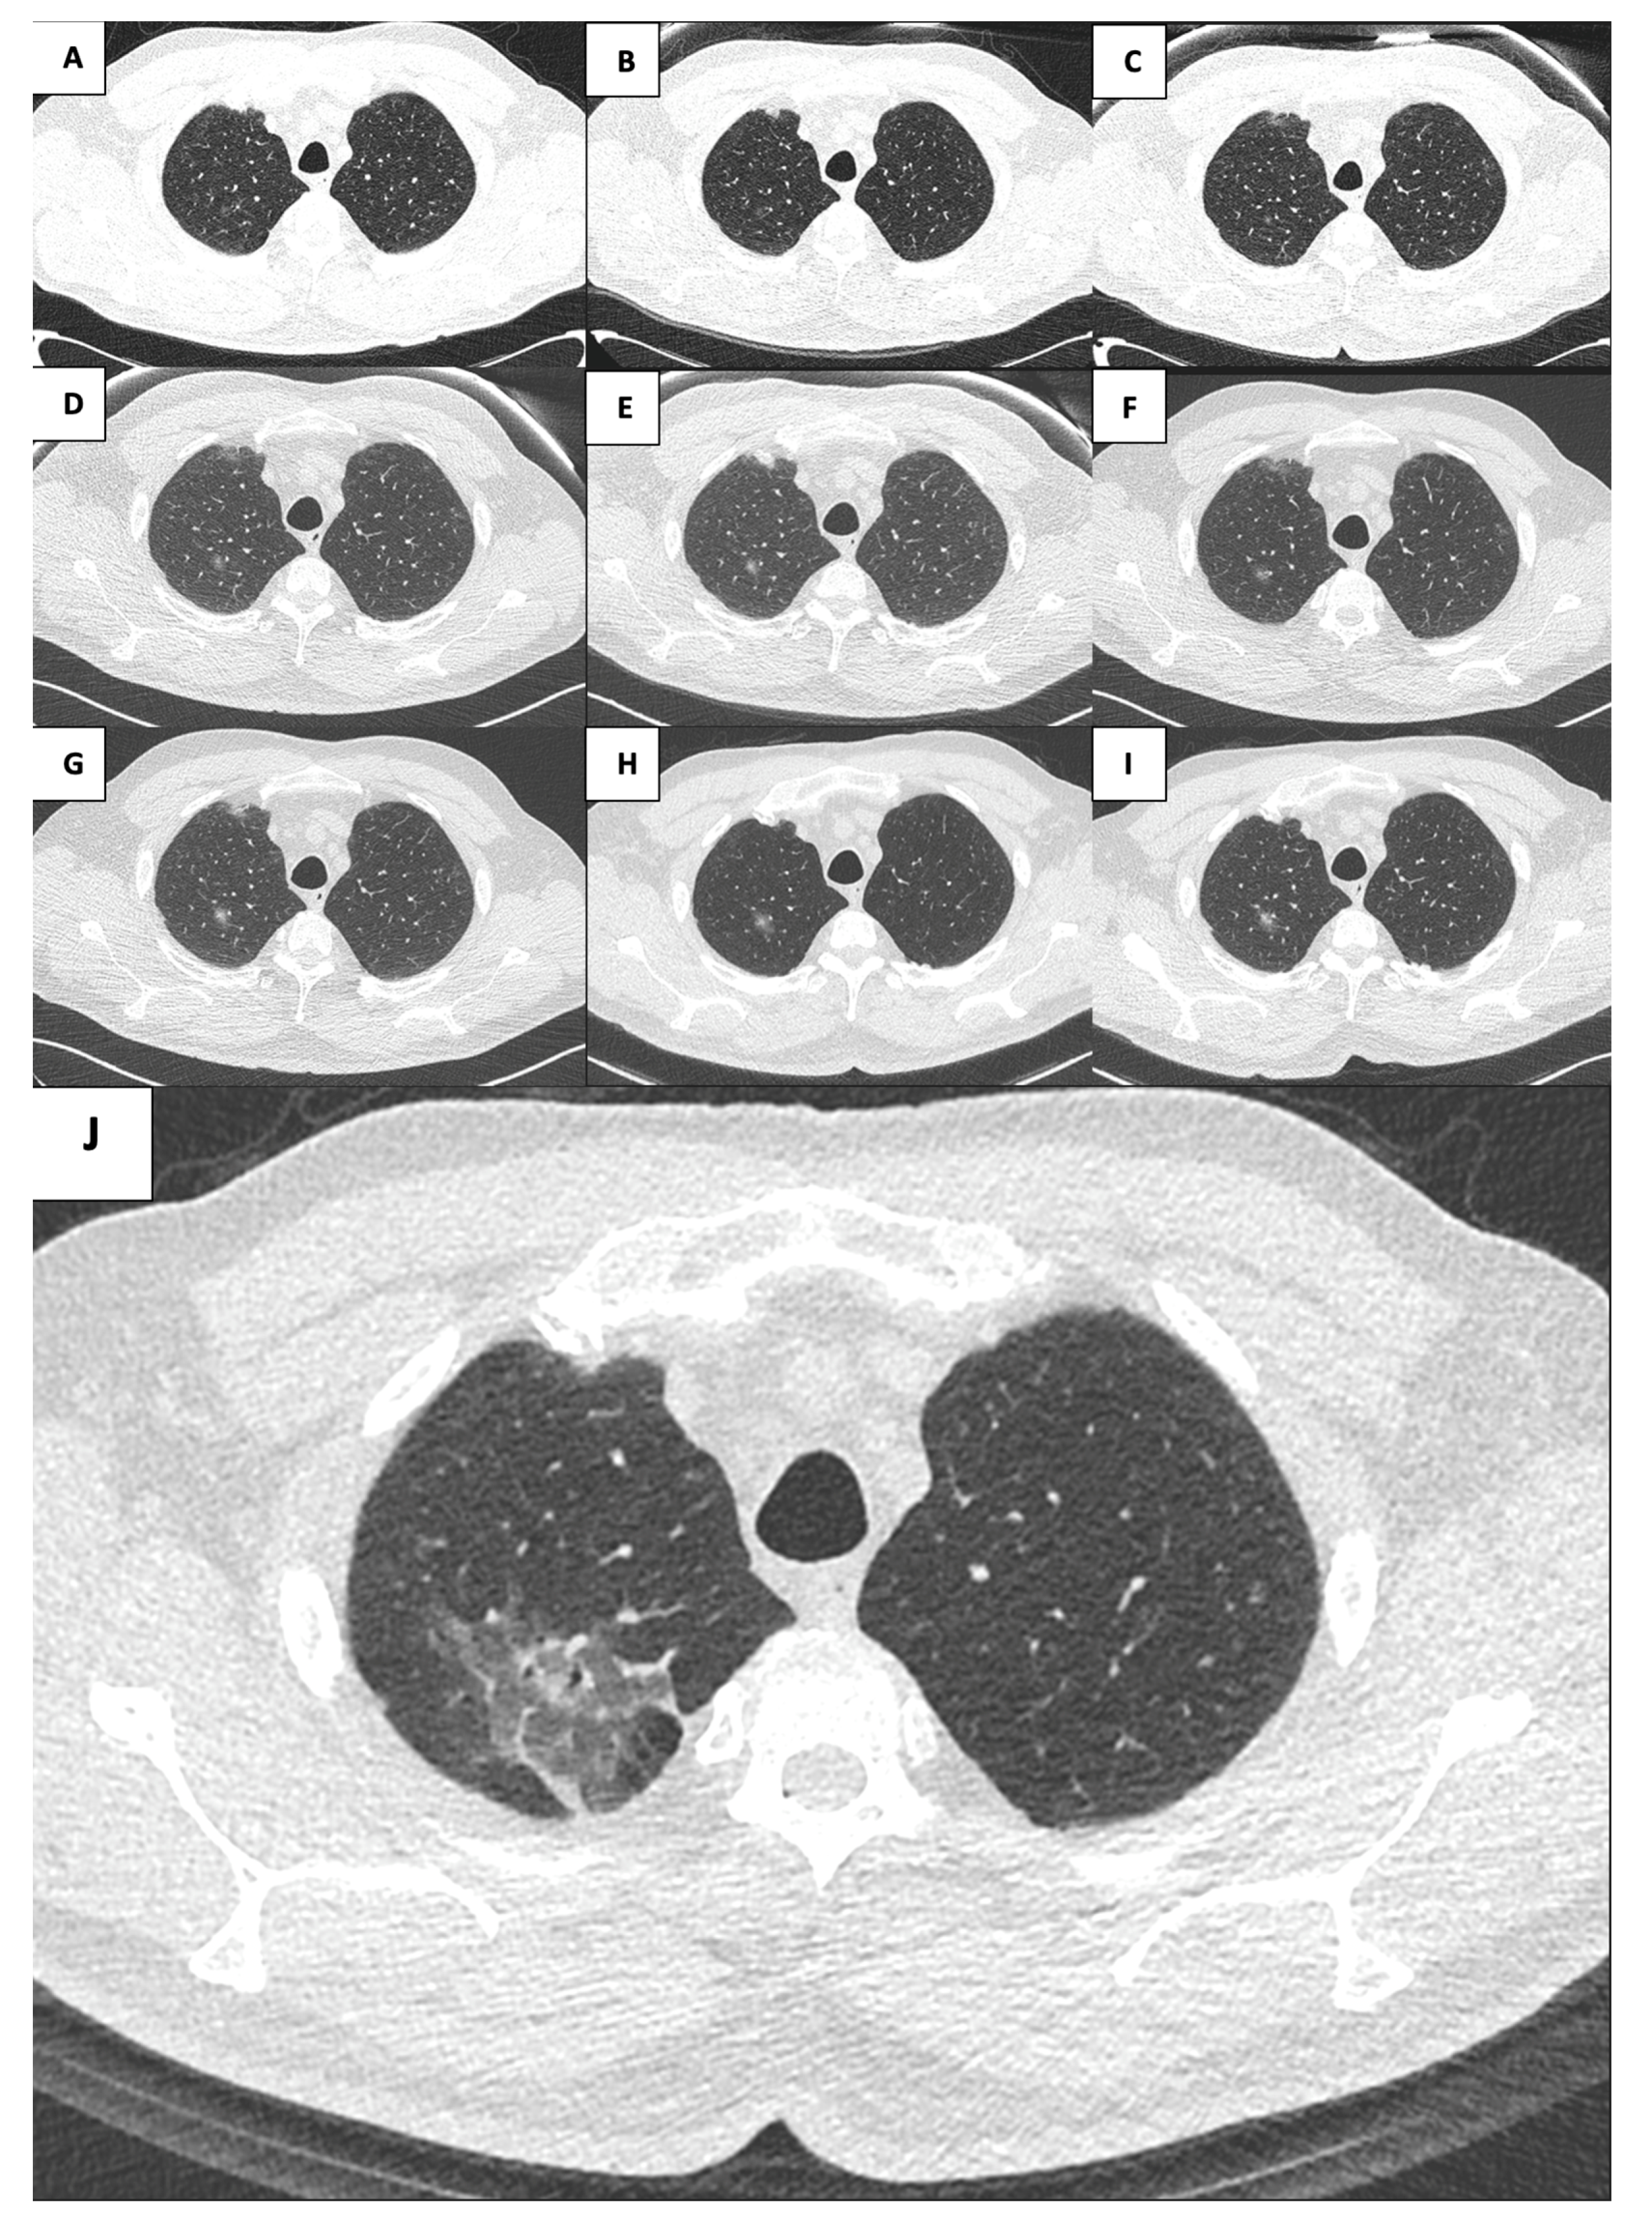

A 71-year-old male patient, a great former smoker without any noteworthy comorbidity, was enrolled in the BioMILD LCS program in 2015. The BioMILD was a prospective trial investigating the combination of LDCT and plasma microRNAs to enhance the effectiveness of LCS through tailored screening intervals and a personalized risk assessment [9]. At the baseline LDCT scan, less than 1 cm of pure GGO of the right upper lobe of the lung was noted. Previous CT scans of the patient have been retrieved and retrospectively reviewed, revealing the presence of the identified GGO in 2005, with minimal dimensional differences; therefore, the lesion was placed under surveillance. Over the years, the GGO was substantially stable, without significant dimensional or densitometric variations (Table 1). In 2020, the solid component seemed to increase, and an FDG-PET was performed, without pathologic tracer uptake. Therefore, surveillance was resumed. The next year, the result of the LDCT was astonishing: the known GGO developed into a 5 cm mixed GGO, with a consistent solid component (1 cm) and fissure shrinkage (Figure 1), presenting a volume doubling time (VDT) of 233 days. An FDG-PET was performed, showing an increased and diffuse tracer uptake within the pulmonary lesion (Figure 2). The patient was completely asymptomatic, without any sign of current or past infection, and was offered VATS surgical excision of the lesion, driven by the concern that the diagnosis might have been delayed too much. During the procedure, the GGO was not detectable; therefore, upfront right upper lobectomy and hylo-mediastinal lymphadenectomy were performed. The postoperative course was complicated by the occurrence of chylothorax on the first postoperative day (POD), which was conservatively managed through fasting, parenteral nutrition, and intravenous somatostatin, leading to progressive resolution. The chest drain was removed on the 15th POD, and the patient was discharged the next day in good clinical condition. The histologic examination revealed that the excised lesion consisted of a non-mucinous AIS of 1.2 cm, within a 4 cm area of fibrotic and congested lung parenchyma at stage pTis pN0 (0/25). Three years later, eighteen years after the first occurrence of the GGO, the patient is alive without evidence of disease.

Figure 2. Evolution of FDG uptake within the right upper lobe lesion ((A): 2020; (B): 2021).